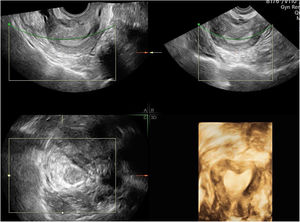

Diagnostic evaluationThe vaginal ultrasound revealed a retroverted uterus of 57mm×27mm×34mm (Fig. 1). Internal contour showed a 7mm indentation compatible with septum. Endometrial thickness was 5mm. Right ovary was nor visualized, nor left one. No free liquid was observed at Douglas space. A pelvic magnetic resonance was requested and absence of the ovaries was confirmed (Fig. 2). At that time, due to the suspicion of an underlying syndromic alteration, a genetic study was requested and reported a 46XY karyotype as well as a heterozygous mutation of variant c 1432+4C>T in intron 9 of the WT1 gene (IVS9+4C>T; NM:024426.4), which was diagnostic of Frasier syndrome.